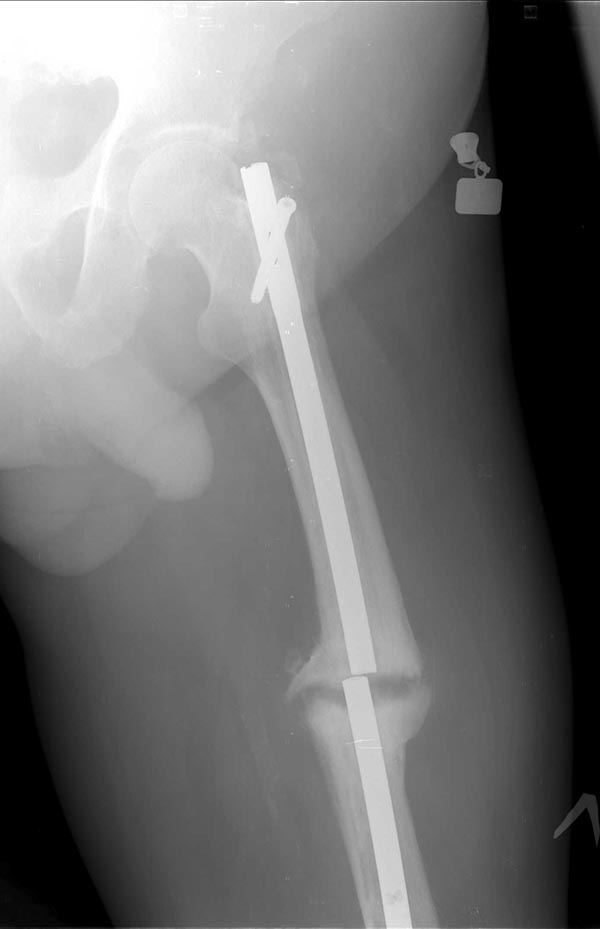

Коротко о пациенте: Возраст 60 лет, мужчина. Со слов травма в 2006

года-ДТП (сбит автомашиной) - в январе 2007 г. выполнено БИОС левого

бедра , затем по неизвестным причинам в 2008 году реостеосинтез левого

бедра штифтом ( снимков нет). Оперирован в одном из городов Сибири.

На снимках( это снимки январь 2015г), которые выложил, определяется

гипертрофический ложный сустав с/3 бедренной кости, перелом штифта на

уровне перелома, штифт канюлированный.Состояние больного